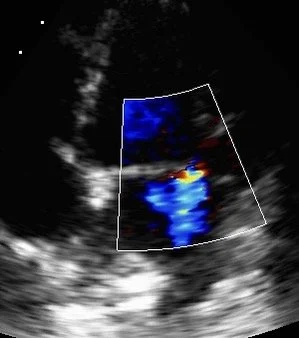

Annotated echocardiography scan of cat heart

Echocardiography scan example with highlight